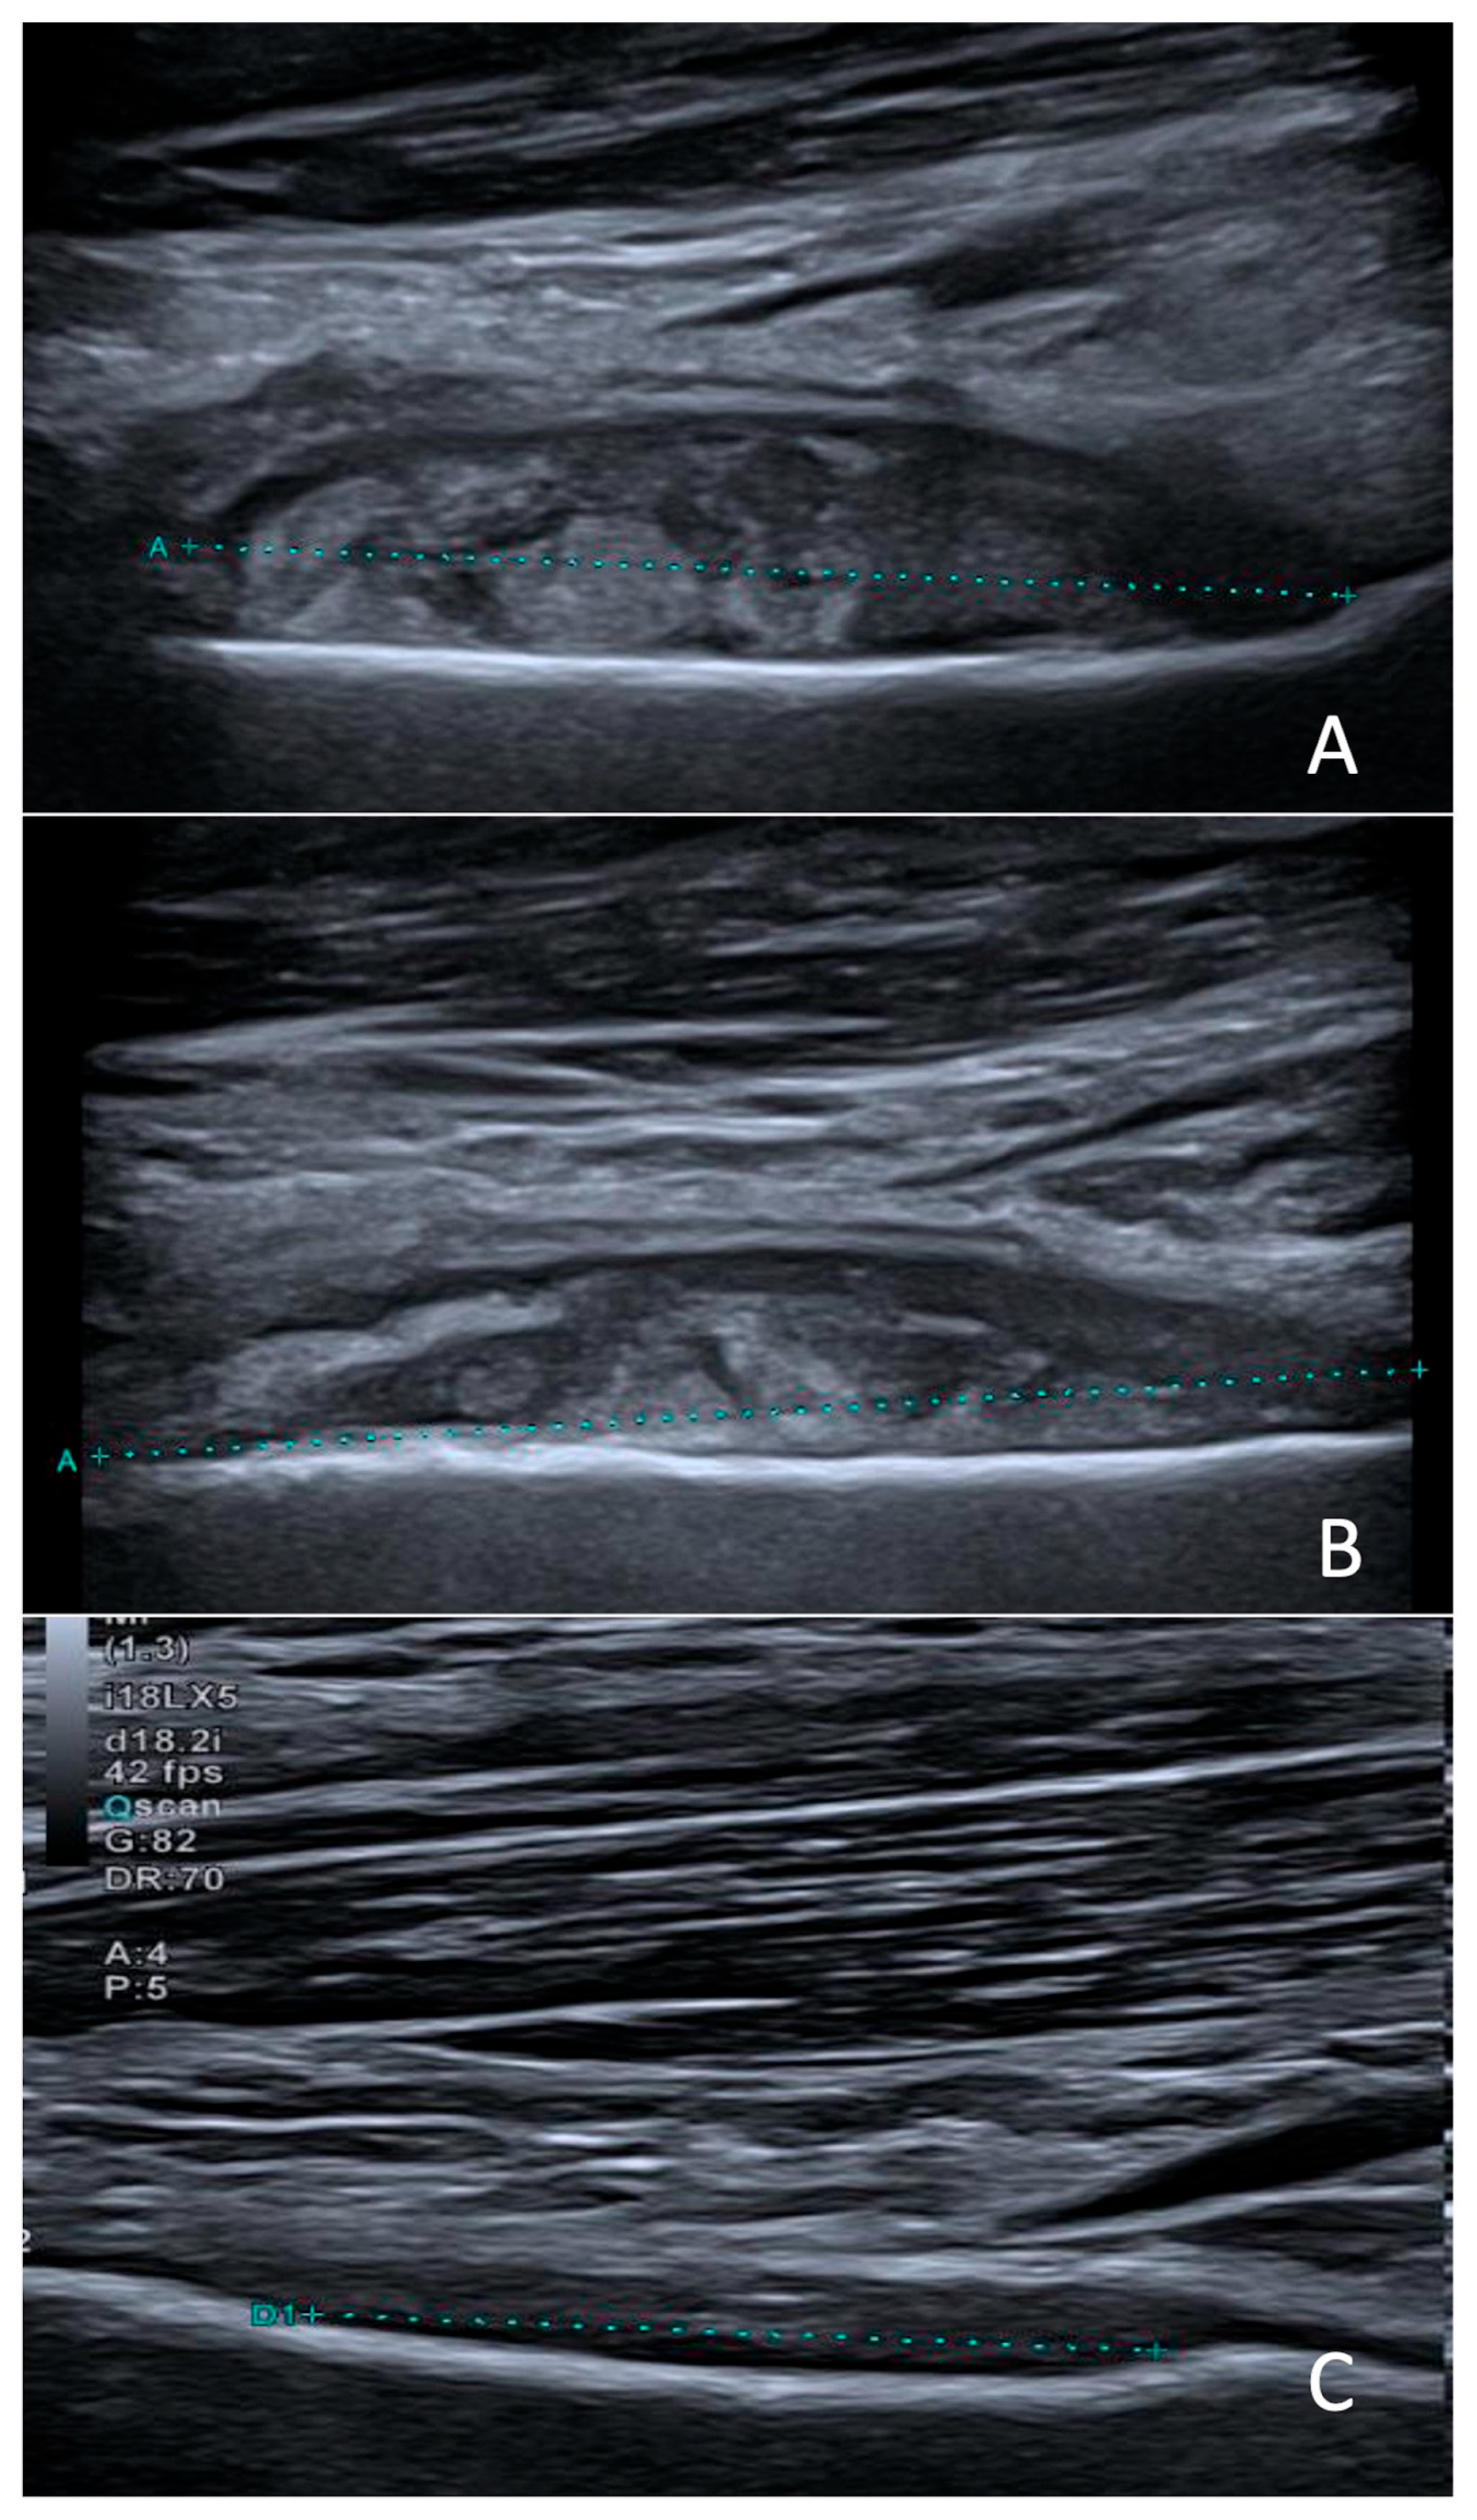

Imaging showed a very thin fluid layer in the right subquadriceps bursa on knee ultrasound. On day 5 of hospitalization, given the good clinical and biological evolution (reduced lameness and CRP decreased to 47 mg/L), oral amoxicillin for 7 days (100 mg/kg/day in 4 doses) was prescribed, and outpatient follow-up was arranged. Radiological evaluation was completed with an MRI of the knee, showing a subperiosteal collection in the distal third of the posterior part of the right femur (Figure 1).

Figure 1. Sagittal MRI slices of the right knee, T2-weighted (A) and T1-weighted (B), showing a heterogeneous subperiosteal fluid collection (large arrows) and the presence of lymphadenopathy (small arrows).